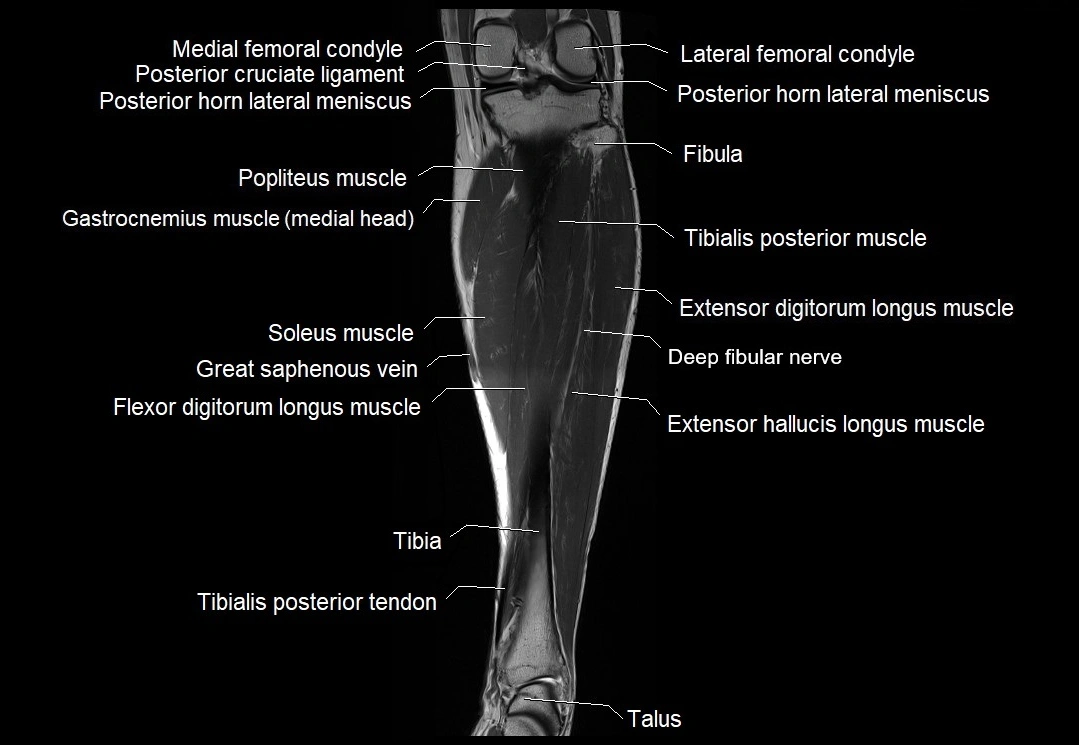

MRI image